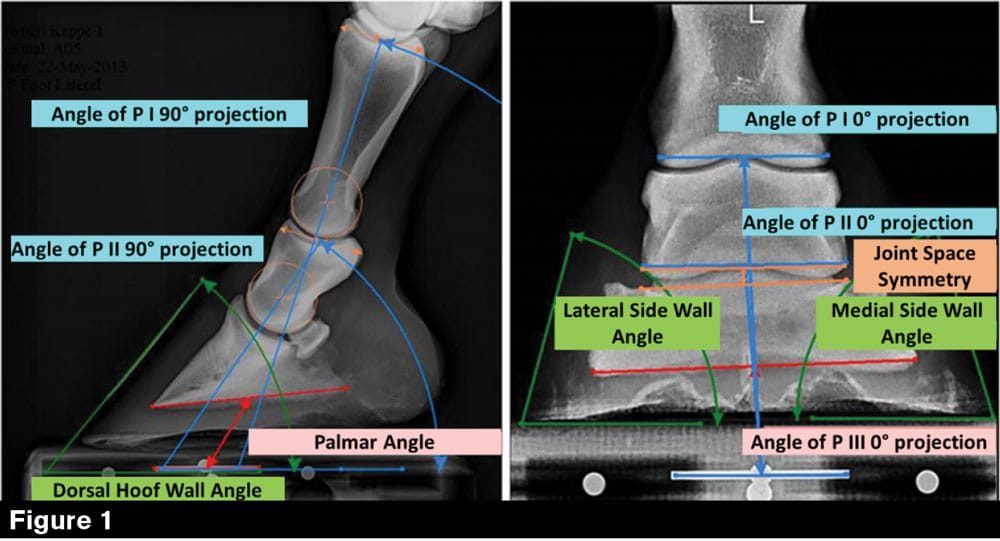

The main goals of hoof trimming are to promote the soundness of the hooves and the limbs, to support the biomechanical efficiency, and maintain functionality of the equine foot.1,2 However, there is no agreement on how to achieve these goals. A wide range of trimming methods exists, and no other topic is so controversially and emotionally discussed as how to ideally trim the equine hoof.3–5 This might be related to the fact that very limited scientific studies directly focused on the effect of hoof trimming on the biomechanics of the equine distal limb exist.

Literature shows that some studies have examined the effect of trimming on kinematic, kinetic, and morphometric parameters.6–8 However, comparative studies, directly examining the influence of different trimming methods on static and dynamic mechanics of the equine toe, are missing. Moreover, no comprehensive…